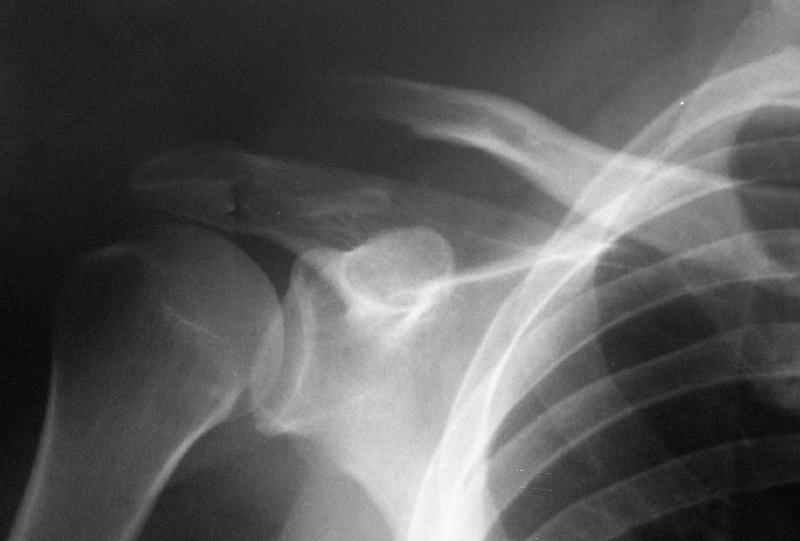

Re: Несросшийся перелом ключицы

"Толкатель" - укороченная спица с упором. На первичных снимках - оскольчатый перелом, отдельный фрагмент с местом прикрепления кл-кл связки сместился каудально.